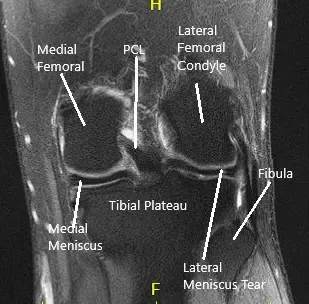

MRI of the left knee suggested a lateral meniscal tear.. There was mild partial-thickness cartilage loss along the central trochlear groove and in the lateral compartment.

MRI of the Knee in coronal and sagittal sections